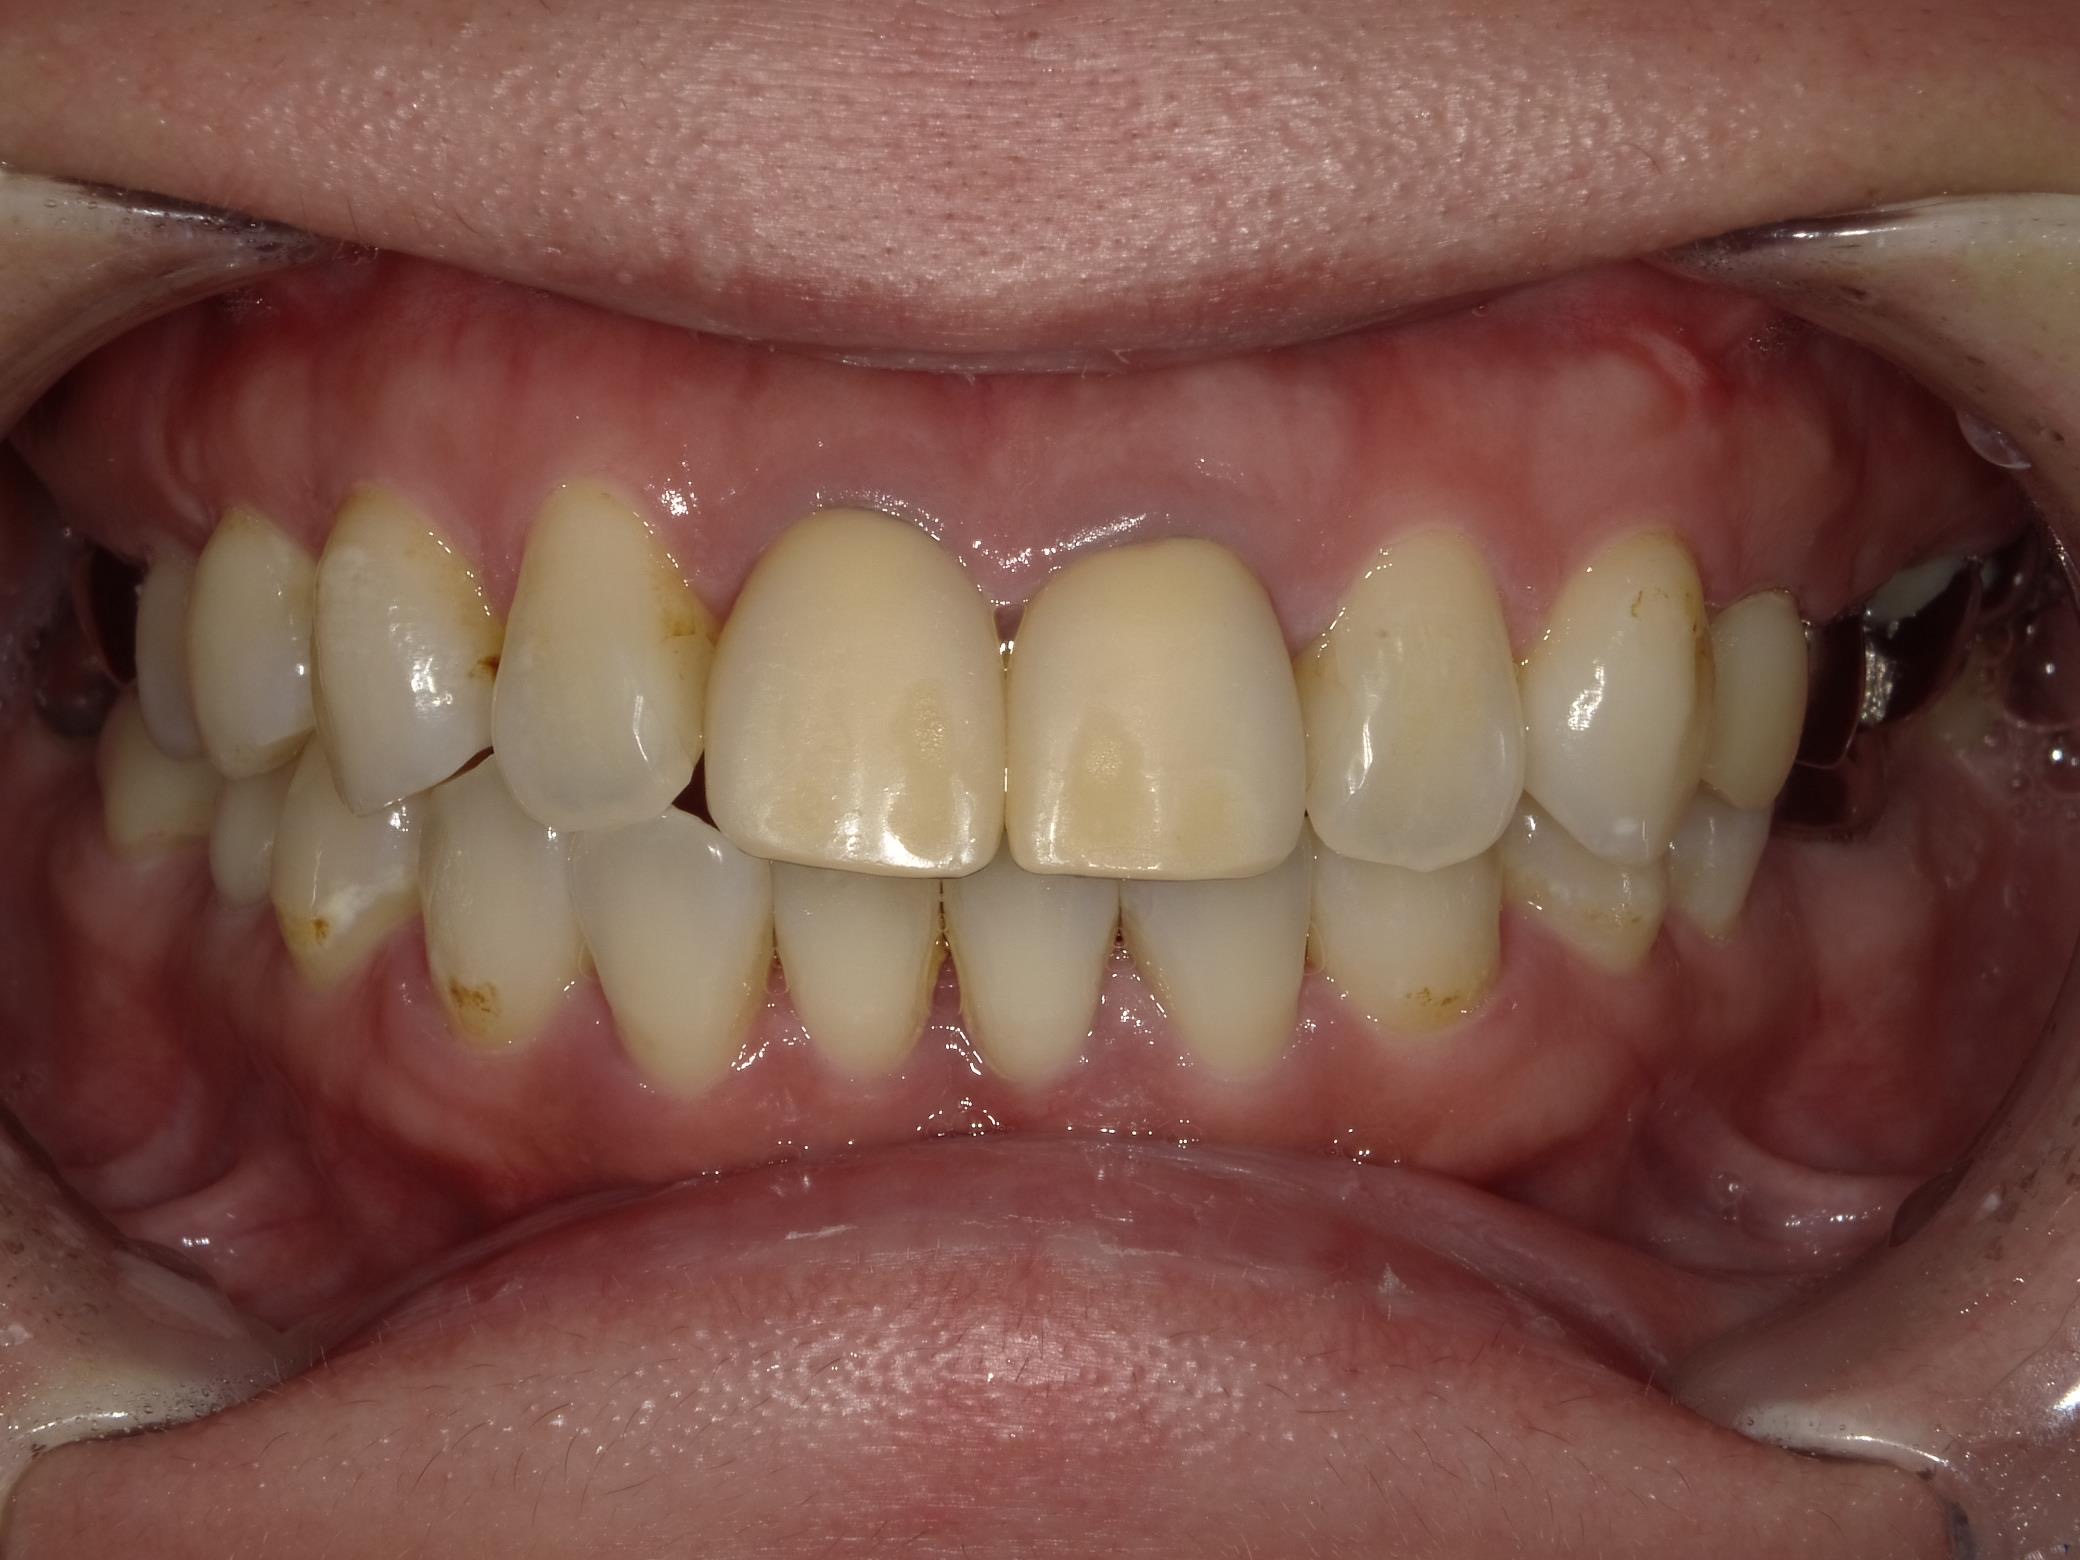

レントゲン、口腔内写真

セラミック治療を進めていく際には、患者様の目指しているゴールを明確にして、あとは根のコンディションがどうなのか?歯茎のコンディションはどうなのか?を考慮して、最終的なゴールを決めていきます。

- 口腔内写真

検査お疲れ様でした。確かに黄ばんでしまっていますね。

そうなんです。この黄ばみが気になってしまって。あと歯茎のふちが黒くなっている事も気になって。